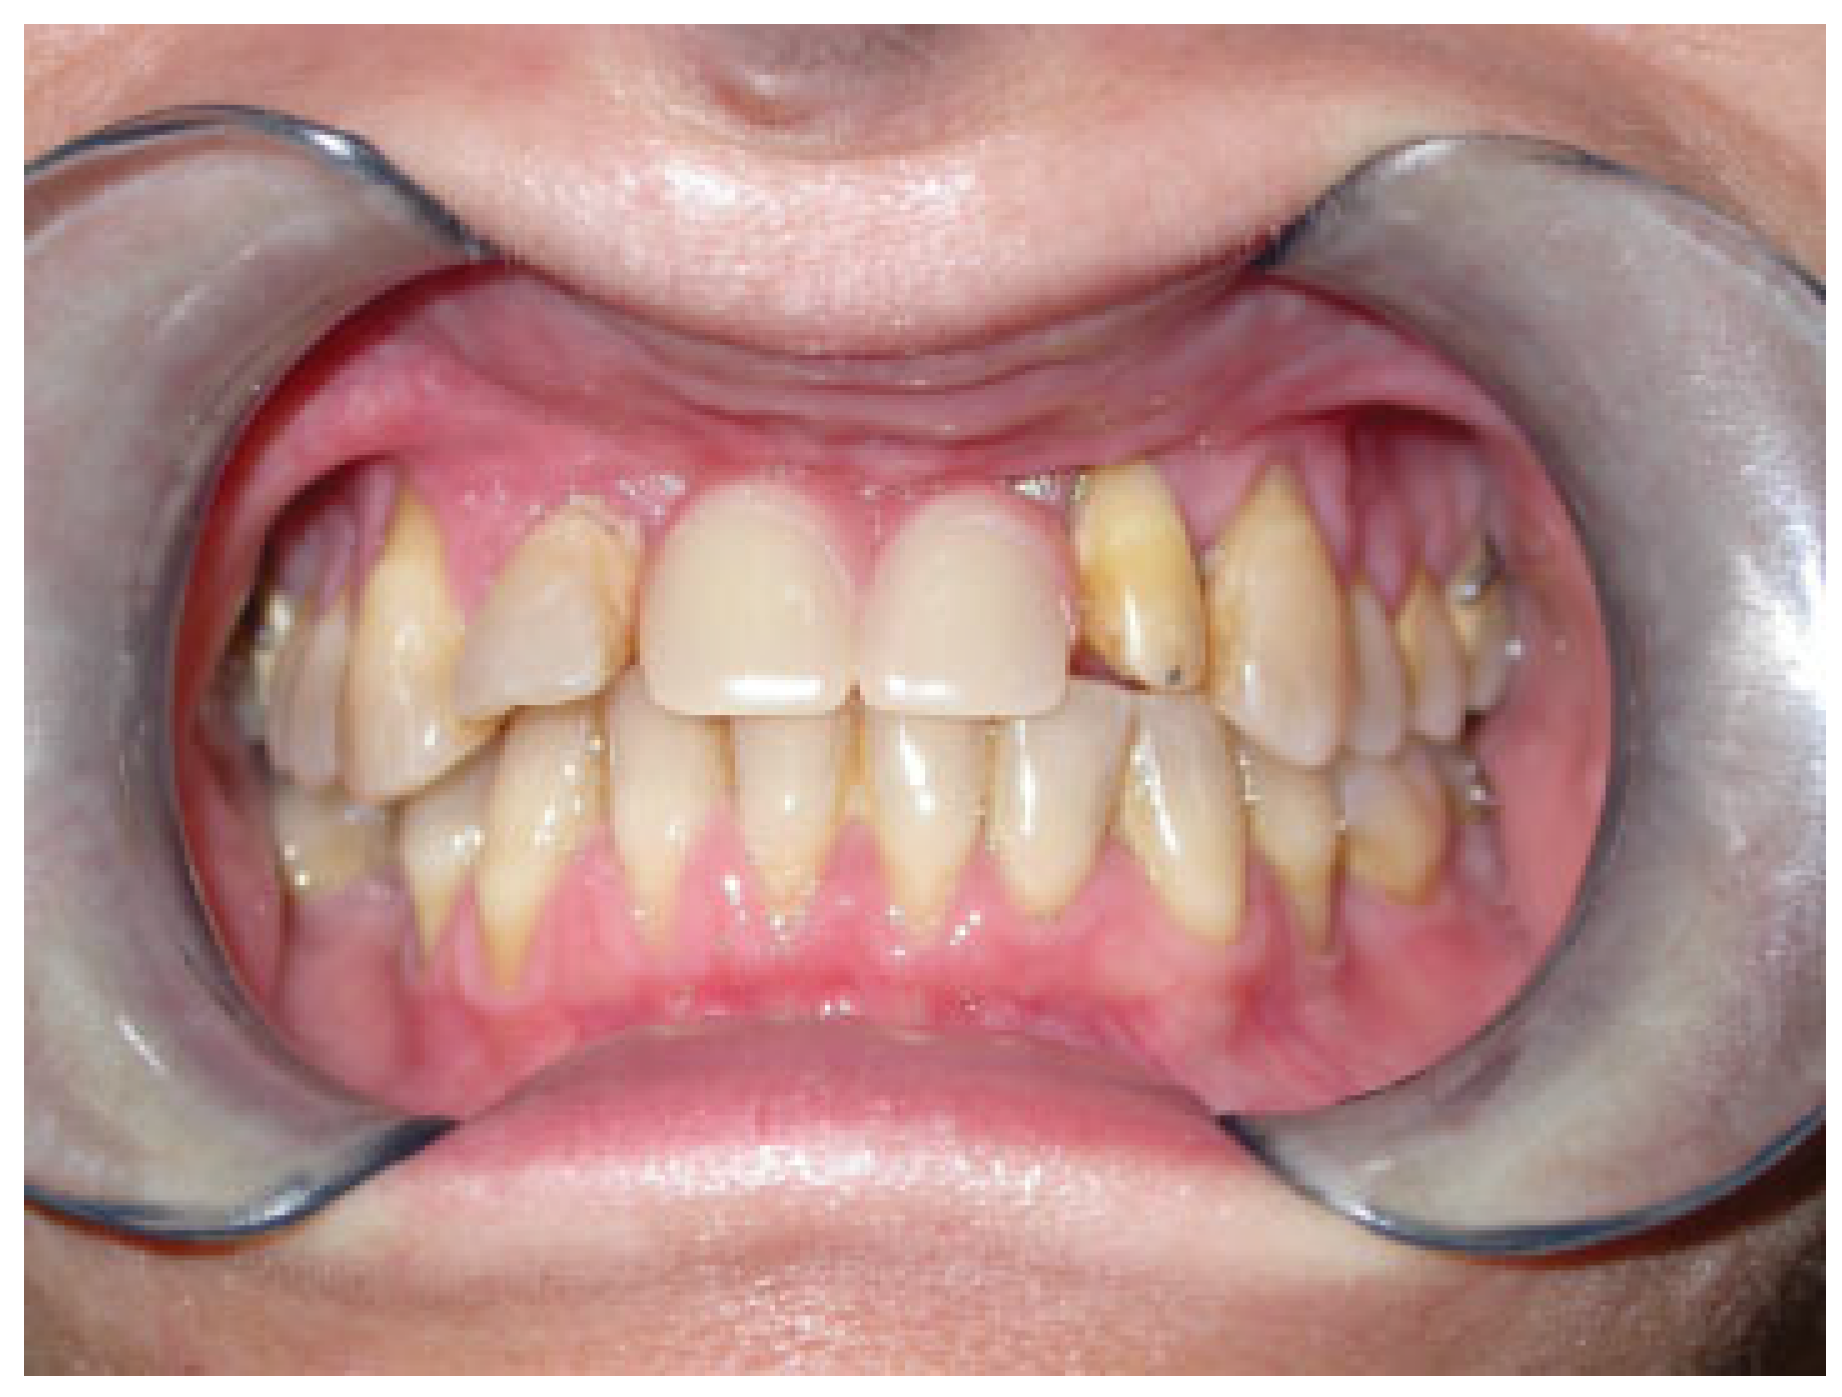

A 52-year-old woman with an unremarkable medical history presented with a severe maxillary atrophy. Upon examination, her skeletal profile revealed a class III skeletal pattern and an edentulous premaxillary sector. She requested a dental rehabilitation. Also, she was concerned about establishing a more aesthetic and younger appearance if possible. In cases like this, our surgical technique of choice is dental rehabilitation with osteointegrated implants prior to Le Fort I maxillary osteotomy for skeletal profile correction. The surgical procedure is performed as the standard model. The osteotomy fragment is displaced inferiorly and anteriorly, followed by rigid internal fixation. Inferior displacement aids in solving the facial height discrepancy, and anterior displacement is required for sagittal discrepancy correction. Osteointegrated implants could be placed simultaneously or at a second visit.

Hereby, we propose a simplified surgical technique with an immediate postoperative positive impact and a promising success rate. Our simplified surgical steps follow. (1) Begin with transposition of the maxillary inferiorly and anteriorly after Le Fort I osteotomy. (2) We emphasize the significance of achieving stable occlusion. (3) Then, we proceed with intermaxillary fixation. The distance of maxilla transportation needs to be planned preoperatively. (4) Next is rigid internal fixation of the dentoalveolar fragment using a customized titanium plate preoperatively. (5) With a tungsten bur, the nasal surface of the maxillary is regularized. (6) Bone grafting blocks are then placed within the gap created by the osteotomy in obtaining the planned vertical height. (7) The bone grafting blocks are fixed in place using a wire that goes beyond the graft and anchors to the custom-made plates (Figure 1 and Figure 2). (8) Finally, check on the maxilla in its new position and new occlusion (Figure 3 and Figure 4). The wire fixation of the grafts allows us to simplify the surgical step of the maxillary repositioning in addition to ensuring the stability of the bone grafts.

Figure 1.

Fixation of the bone blocks with a wire that goes beyond the graft and anchors the plates.